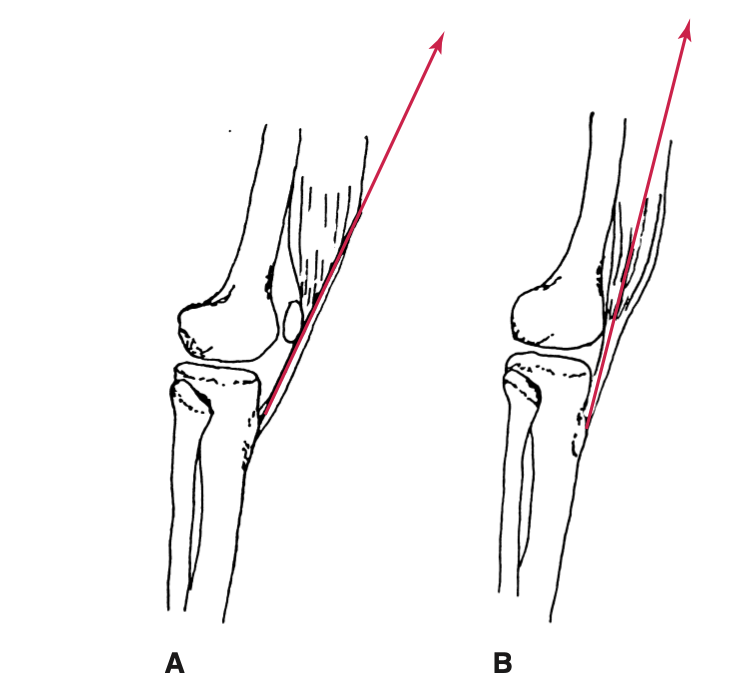

* Góc Q:

Là góc giữa một dường từ gai chậu trước trên của xương cánh chậu đến giữa xương bánh chè và một đường từ giữa xương bánh chề đến lồi củ chày. Góc Q tốt nhất cho hoạt động của cơ tứ đầu đùi là khoảng 10° vẹo ngoài. Góc Q bình thường ở nam là 10° đến 14° , nữ từ 15° đến 17°.

Góc Q tạo lực ép vẹo ngoài lên gối, và nếu quá lớn có thể gây các vấn đề bánh chè đùi. Góc Q > 17° được xem là quá mức và được gọi là gối vẹo ngoài (genu valgum) hay chân chữ X. Góc Q rất nhỏ gọi là gối vẹo trong (genu varus), chân hình chữ O.